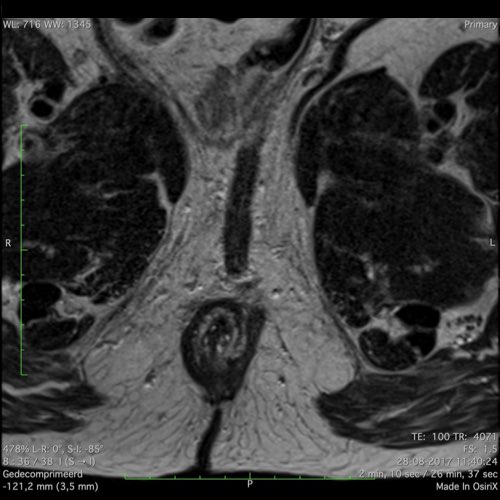

Đặc điểm MRI

- Thường khó xác định

- Thường biểu hiện nhưdày thành ruột lan tỏa, đoạn dài

- Kiểu tăng trưởng dưới niêm mạc, cho ra mộtHình ảnh “bia” (target)trên các hình ảnh cắt ngang

- Thâm nhiễm mỡ trực tràng lan tỏalà phổ biến

Hình ảnh

Các hình ảnh được cung cấp cho thấy ung thư biểu mô tế bào nhẫn với tình trạng dày lan tỏa thành trực tràng, hình ảnh bia bắn điển hình, và sự xâm lấn mỡ mạc treo trực tràng.